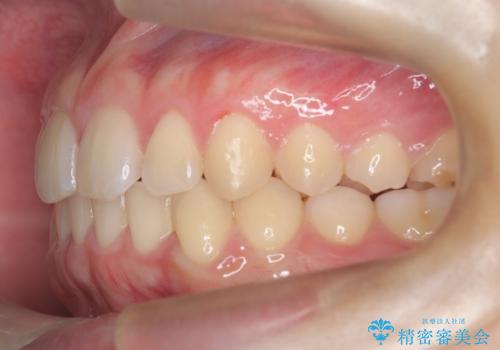

マウスピース矯正で前歯のガタツキを改善! 短期間で治療完了

- 1年3ヶ月

- 前歯のガタツキが気になるとのことで来院されました。

マウスピース矯正で治療することとしました。